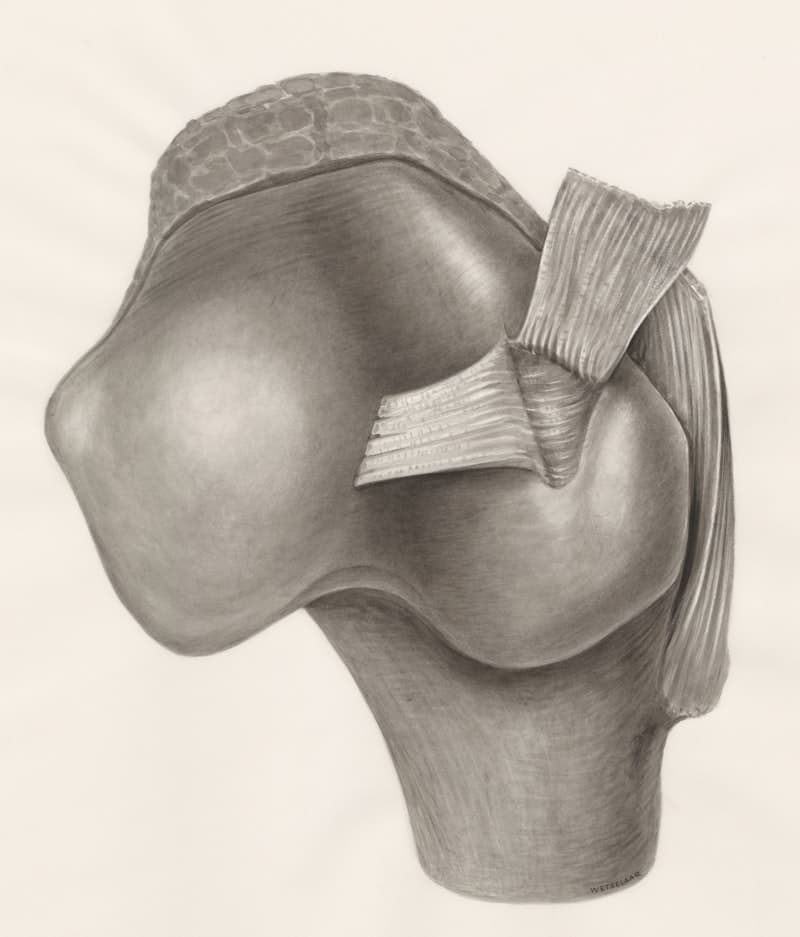

Lesión del cartílago (labrum) en el hombro o la cadera, que causa dolor, inestabilidad y movimiento limitado.

Rigidez y movimiento reducido del hombro debido a la inflamación de la cápsula del hombro.

Condición donde el movimiento del hombro causa compresión de tendones o bursa.

Condición del hombro donde los tendones del manguito rotador están irritados o inflamados.